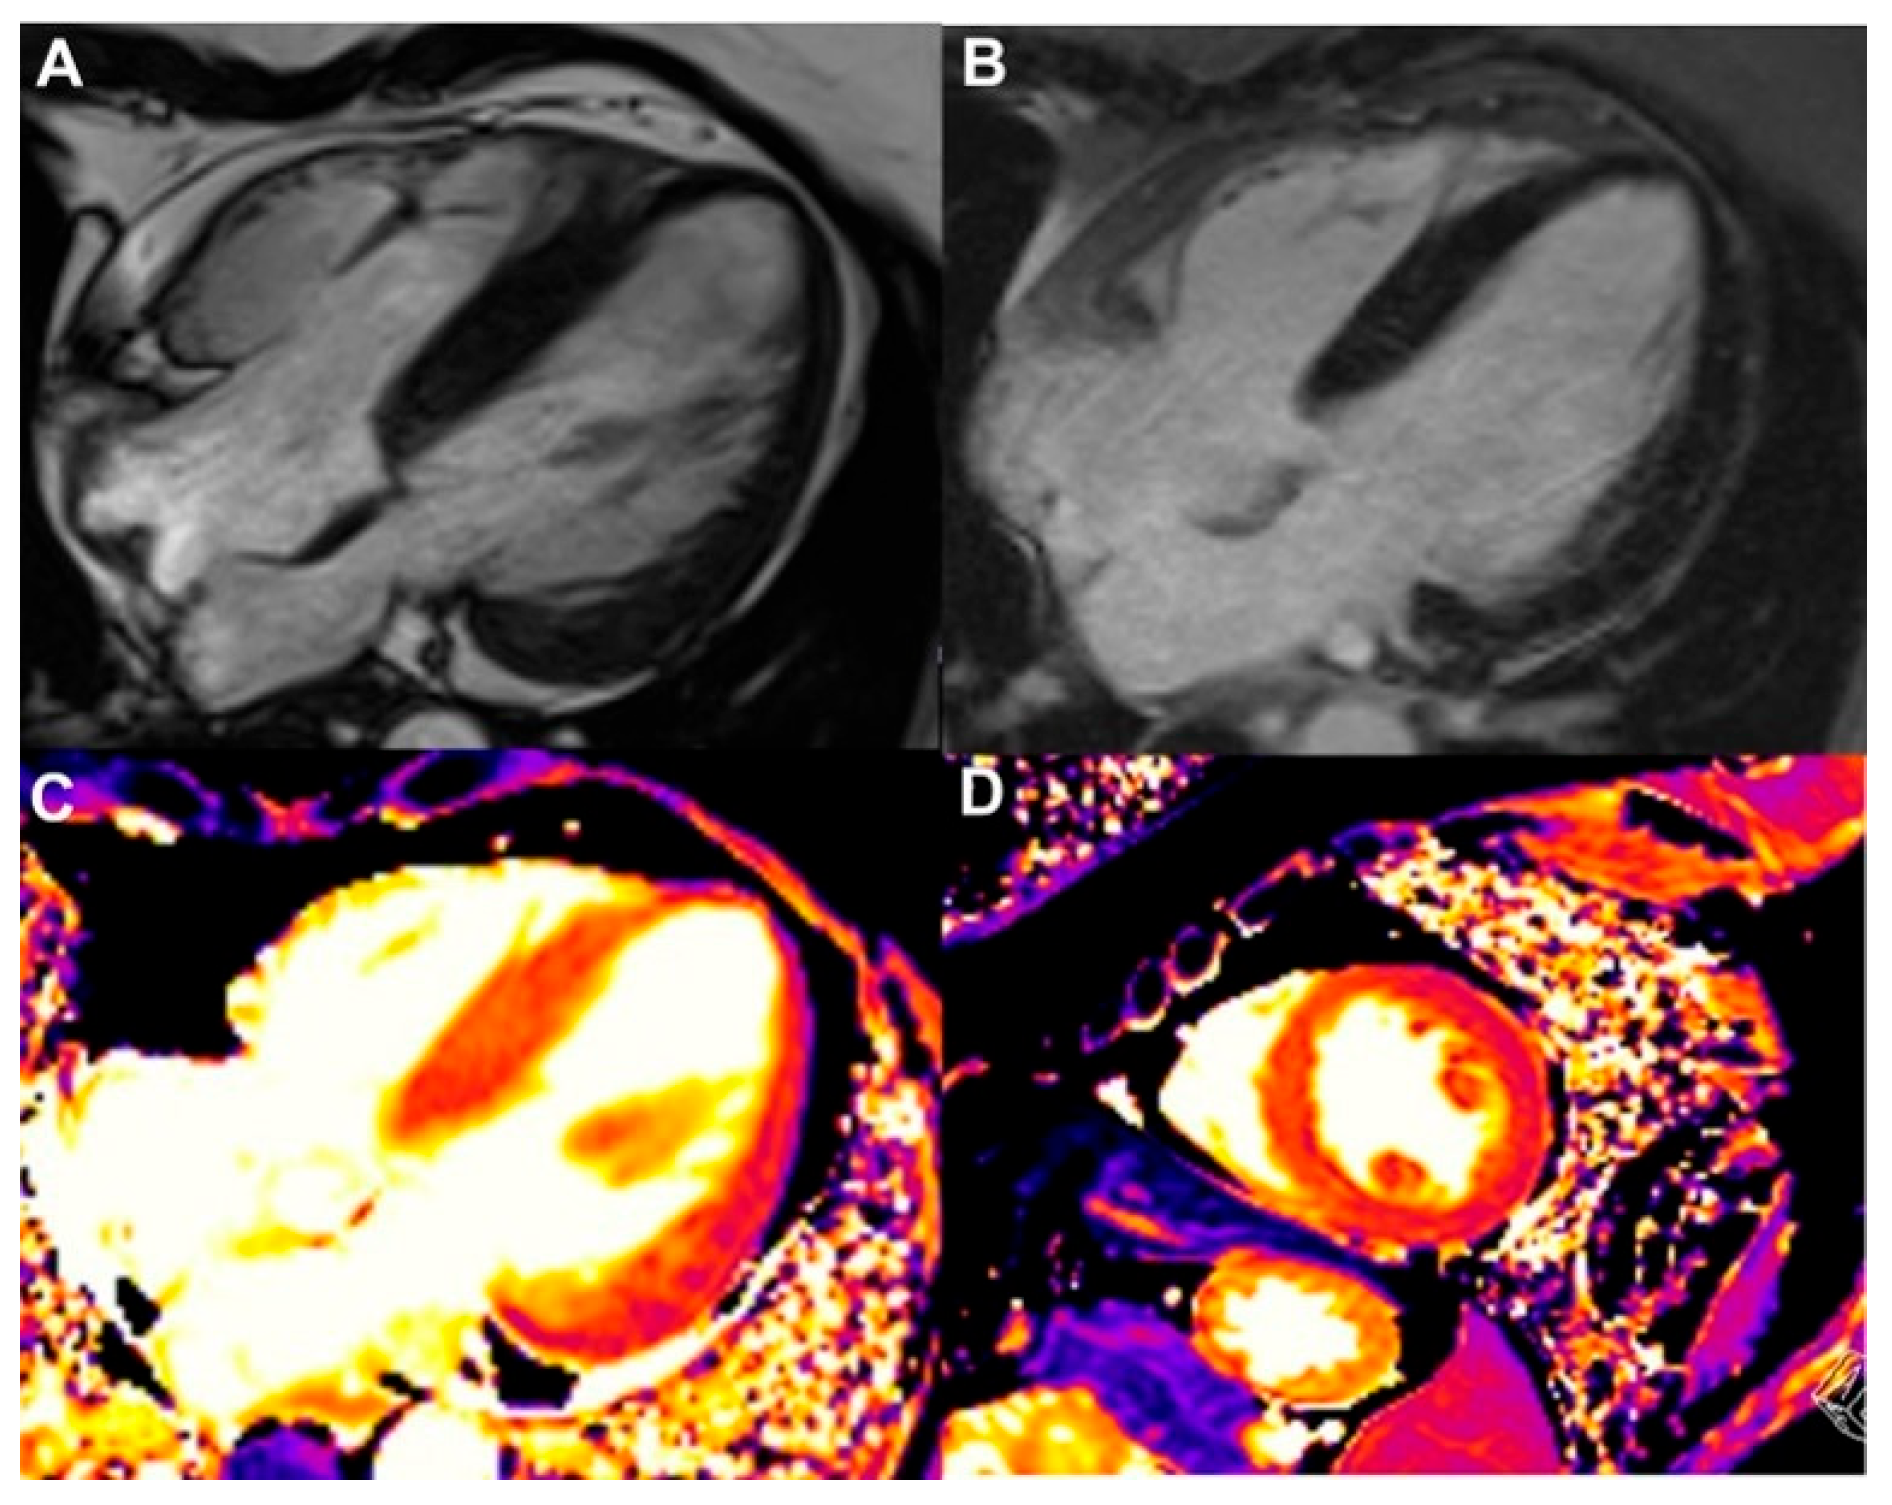

- Thavendiranathan, P.; Zhang, L.; Zafar, A.; Drobni, Z.D.; Mahmood, S.S.; Cabral, M.; Awadalla, M.; Nohria, A.; Zlotoff, D.A.; Thuny, F.; et al. Myocardial T1 and T2 Mapping by Magnetic Resonance in Patients With Immune Checkpoint Inhibitor–Associated Myocarditis. J. Am. Coll. Cardiol. 2021, 77, 1503–1516. [Google Scholar] [CrossRef]

- Ferreira, V.M.; Schulz-Menger, J.; Holmvang, G.; Kramer, C.M.; Carbone, I.; Sechtem, U.; Kindermann, I.; Gutberlet, M.; Cooper, L.T.; Liu, P.; et al. Cardiovascular Magnetic Resonance in Nonischemic Myocardial Inflammation. J. Am. Coll. Cardiol. 2018, 72, 3158–3176. [Google Scholar] [CrossRef]

- Burrage, M.K.; Ferreira, V.M. The Use of Cardiovascular Magnetic Resonance as an Early Non-Invasive Biomarker for Cardiotoxicity in Cardio-Oncology. Cardiovasc. Diagn. Ther. 2020, 10, 610–624. [Google Scholar] [CrossRef]

- Thavendiranathan, P.; Wintersperger, B.J.; Flamm, S.D.; Marwick, T.H. Cardiac MRI in the Assessment of Cardiac Injury and Toxicity From Cancer Chemotherapy. Circ. Cardiovasc. Imaging 2013, 6, 1080–1091. [Google Scholar] [CrossRef]

- Lerchner, T.; Mincu, R.I.; Bühning, F.; Vogel, J.; Klingel, K.; Meetschen, M.; Schlosser, T.; Haubold, J.; Umutlu, L.; Dobrev, D.; et al. Cardiac Magnetic Resonance Imaging in Patients with Suspected Myocarditis from Immune Checkpoint Inhibitor Therapy—A Real-World Observational Study. IJC Heart Vasc. 2025, 56, 101581. [Google Scholar] [CrossRef]